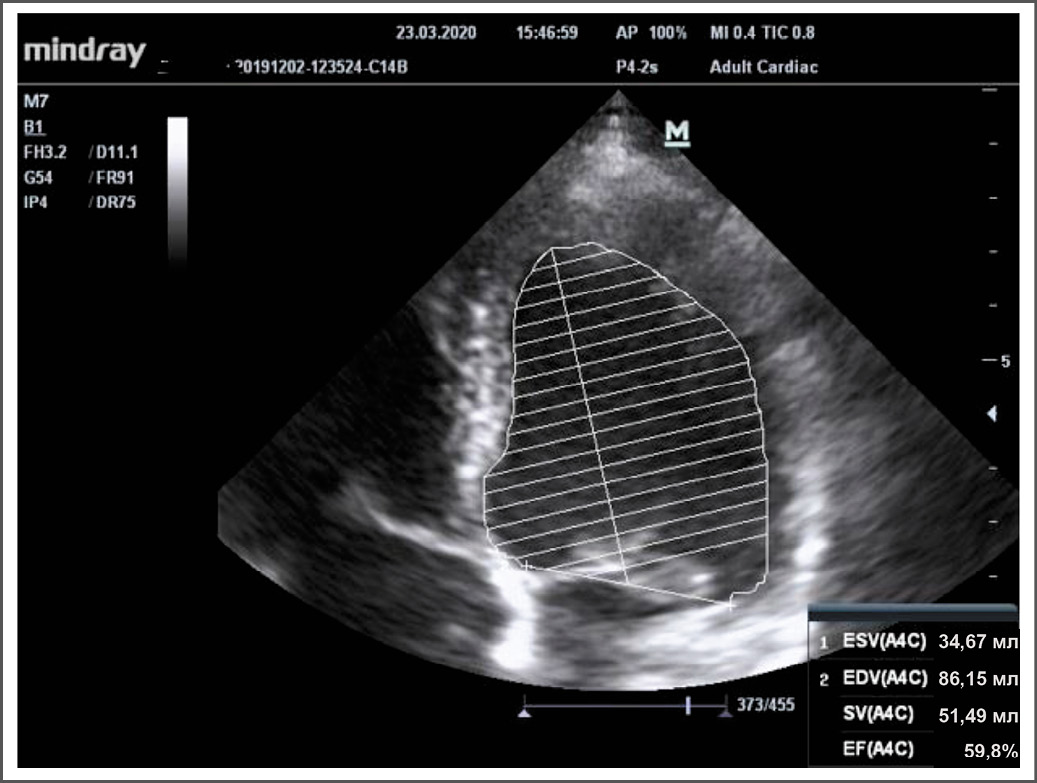

При контрольном обследовании через 3 мес, в марте 2020 года выполнено повторное эхокардиографическое исследование. Зафиксирована положительная динамика по сравнению с исследованием от декабря 2019 года в виде нормализации размеров всех камер сердца, нормализации глобальной систолической функции левого желудочка (фракция выброса по Симпсону – 58%; рис. 3), сократимости правого желудочка, купирования вторичной недостаточности митрального и трикуспидального клапана и уменьшения степени лёгочной гипертензии.

Рис. 3. Эхокардиографическое исследование пациентки Д.Н. через 3 мес после начала лечения. Верхушечное 4-х камерное сечение (нормализация фракции выброса по Симпсону).

Fig. 3. Echocardiography of patient D.N. 3 months after the start of treatment. Apical 4-chamber section (normalization of ejection fraction according to Simpson).